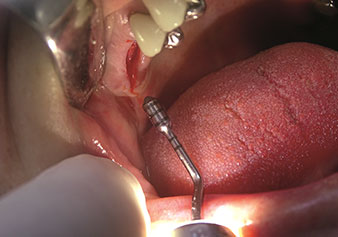

Zustand nach Extraktion mit Piezochirurgie

Abb. 2: Zustand nach Extraktion mit Piezochirurgie. Foto: © Dr Torsten Conrad (Bingen am Rhein)